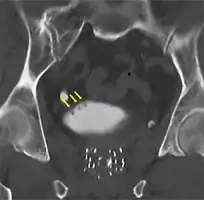

Cystoscopy: multiple papillary tumors on the right side of the posterior wall